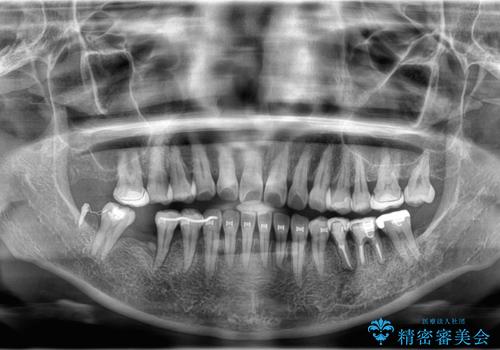

- 歯がぐらぐらしてきて怖いとのことで、当院に来院された患者様です。

右下小臼歯は歯周病で大きな骨欠損を認めていました。

できる限り歯が保存できるように治療したいとのことでエムドゲインを用いた再生治療を行っています。

欠損歯に関しては、奥歯をアップライトさせてインプラント埋入予定です。